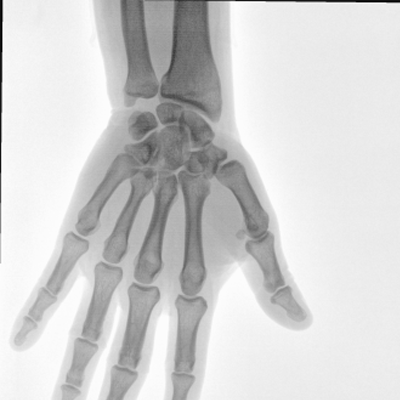

動(dòng)態(tài)板C形臂 開(kāi)啟清晰影像新篇章 PLX118F

臨床適用科室:骨科、普通外科、矯形外科、創(chuàng)傷外科、泌尿外科、脊柱外科、疼痛外科、消化科、婦科等科室。

大尺寸動(dòng)態(tài)平板探測(cè)器,高DQE、低噪聲、圖像清晰。采用多分辨率圖像增強(qiáng)處理技術(shù),不同部位不同圖像處理算法,滿足客戶多樣化的需求。

圖形化操控界面設(shè)計(jì):設(shè)有多種人體特征攝影參數(shù),操作簡(jiǎn)便。雙向紅光十字定位系統(tǒng):實(shí)現(xiàn)無(wú)射線下的高效定位。信息共享:遵循DICOM3.0格式接口,可無(wú)縫對(duì)接云PACS系統(tǒng)。